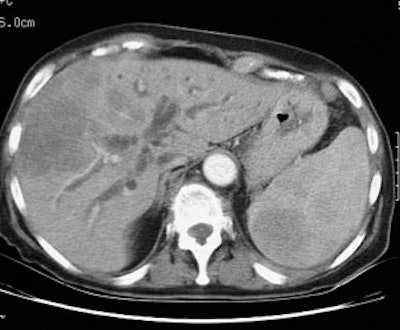

Liver involvement: The FDG PET study below demonstrates hepatic involvement in a patient with widespread lymhoma. The CT scan in this case was positive. Splenic involvement is also evident on the CT scan and was also present on separate slices (not shown) from the FDG study. (Click PET image to view rotating cine file) |

|